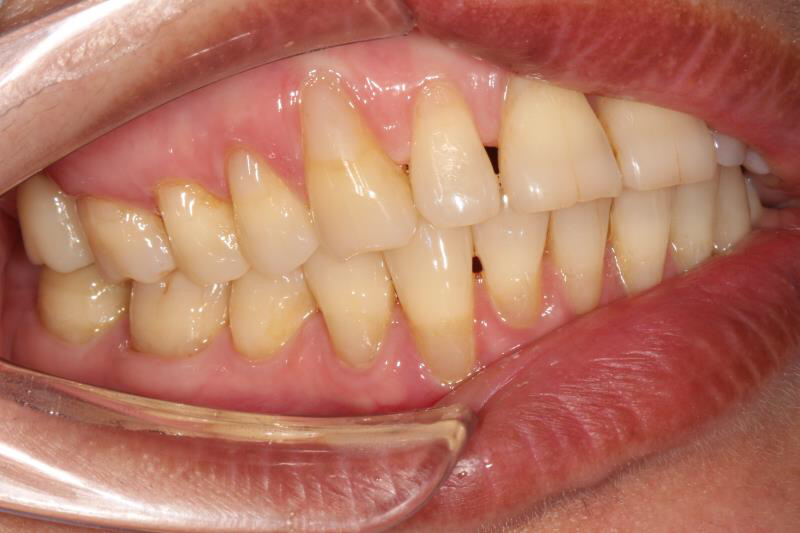

今天给大家分享的病例是一位中年女性,17缺失,由于长时间未修复,47伸长,留给17修复的空间不足。

老卢给她的治疗方案是:17种植修复,47根管治疗后截冠、高嵌体修复。这样可以最大限度的增加患者的咀嚼效率。